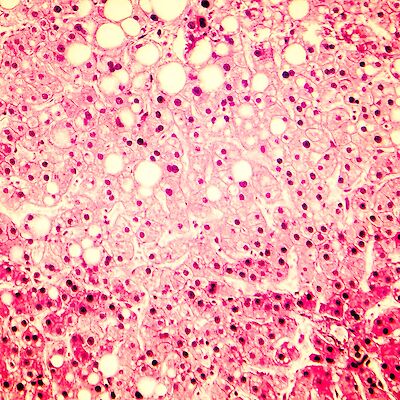

Tulosyynä oksentelu – tapauksen ratkaisu Diagnoosi ratkesi yksinkertaisella verikokeella. Karoliina Wehkalampi, Nina Kaseva Tiede 12.3.2026 Kommentteja

Tulosyynä oksentelu – tapauksen ratkaisu Tiede Tulosyynä oksentelu – tapauksen ratkaisu Diagnoosi ratkesi yksinkertaisella verikokeella.